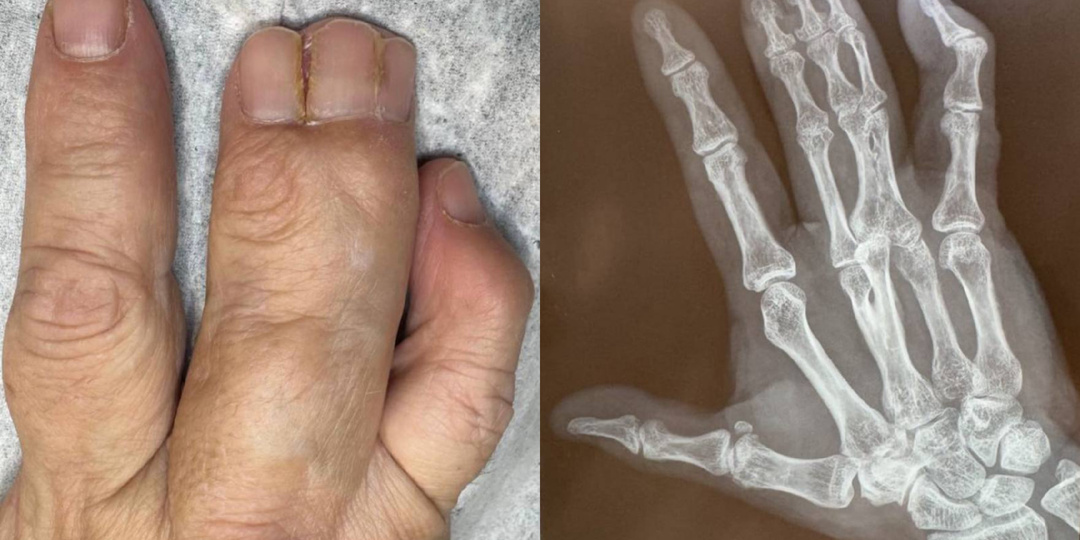

Ноготь медленно растёт, и палец болит

Каждый день к нам обращаются клиенты с гипертрофированным передним валиком и отсутствующей передней частью ногтевой пластины. Часто такие случаи определяют как экзостоз, просто глядя на увеличенный размер переднего валика пальца, особенно на первых пальцах стопы. Но что на самом деле представляет собой экзостоз и как с ним бороться? Экзостоз — это доброкачественное образование новой костной ткани на поверхности костей. Этот термин находит своё применение в различных медицинских контекстах и может быть известен под другими названиями, такими как остеохондрома, хондрома или остеофит. Каковы симптомы экзостоза? Экзостозы могут вызывать различные симптомы, включая: Внешние причины Внутренние причины Осмотр подолога при подозрении на подногтевой экзостоз включает сбор анамнеза, визуальную оценку деформации ногтевой пластины (поднятие, скручивание, онихолизис) и пальпацию, выявляющую твёрдый болезненный нарост. Специалист оценивает степень воспаления, состояние кожи, а для подтверждения диаг